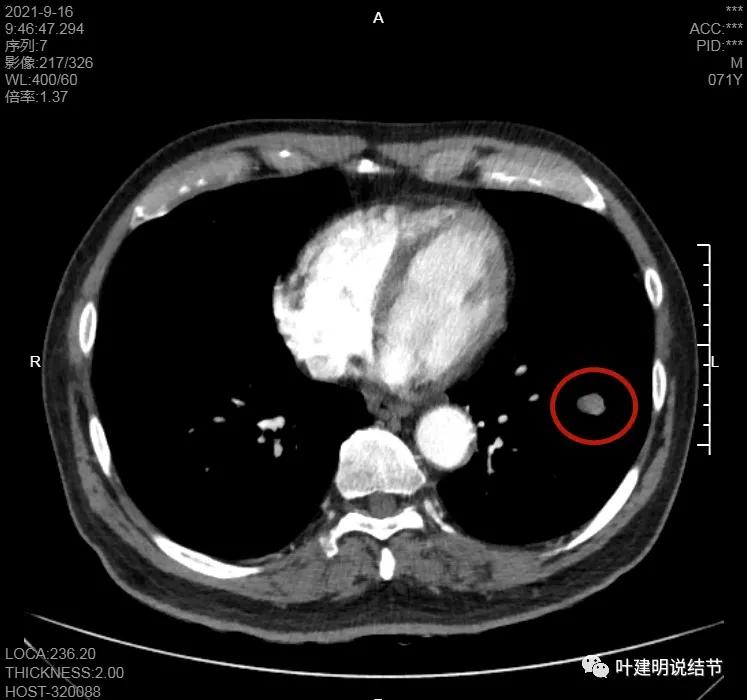

左下病灶在增强CT中强化不明显,但有肺门区肿大淋巴结,而且近3厘米大。同事叫我看片子的时候,本来只先看左下病灶处,以为是良性结节。但翻到肺门区,发现有如此大的肿大淋巴结,那这个原发灶则肯定是恶性的了!我们先来看纵隔窗的淋巴结情况:

左肺门区淋巴结肿大

肺门区淋巴结挤压附近肺血管,但似乎示见肿瘤侵犯破坏血管壁

淋巴结巨大,部分包绕肺血管,但仍未见明显侵犯血管壁